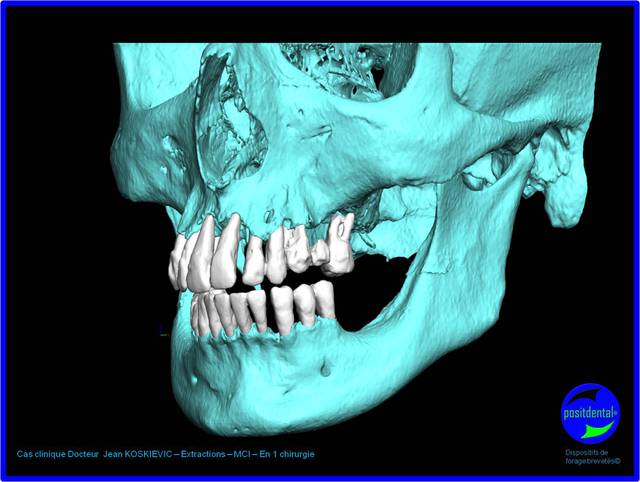

projet prothétique réhabilitation complète implanto porté en MCI, la S.I.A.O permet d'objectivé la faisabilité

-prothèse métallique présent lors du scanner

-mobilité trop importante pour prendre une empreinte du maxillaire